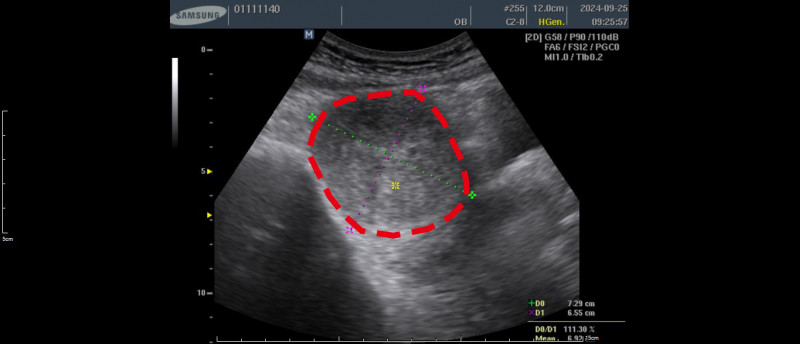

〔記者蔡淑媛/台中報導〕52歲的徐小姐長年經痛、頻尿、夜尿及下腹悶脹等症狀 去年檢查發現子宮前壁長有一顆約7公分大,有如中型芒果大小的子宮肌瘤,已經壓迫膀胱,選擇「子宮肌瘤微波消融術」治療,住院兩日後出院,肌瘤逐漸縮小到只剩1顆小番茄大,症狀也大幅改善。

胡洺褘指出,患者希望保留子宮,並考量恢復期短、疼痛感較低,決定接受自費的子宮肌瘤微波消融術,該手術透過影像導引,將微波能量精準作用於肌瘤組織,使肌瘤壞死並逐漸被人體吸收,屬於微創治療方式。